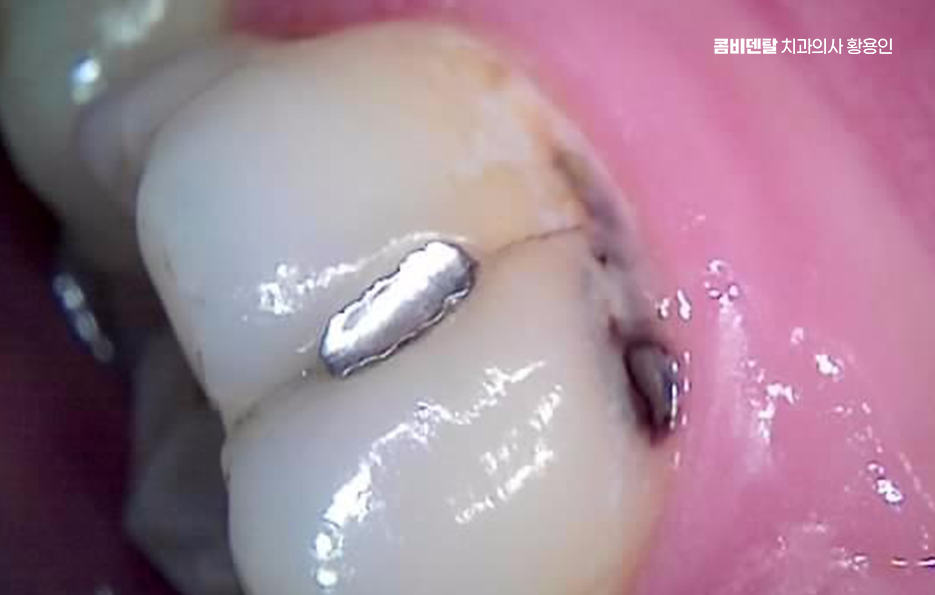

치아 시림 통증 치료 방법은 원인에 따라 달라지며 상아질 노출로 인한 시림은 먼저 자극을 줄이는 것도 중요하고 치경부 마모가 심한 경우에는 레진으로 노출 부위를 덮어 보호하거나 잇몸 퇴축이 심하다면 치주 치료를 통해 염증을 조절하고 추가적인 퇴축을 막아야 할 필요가 있어요

신경 염증이 원인이라면 원인에 대한 치료를 통해 해결해야 하는데 충치를 제거하고 신경 상태를 평가해 신경치료 여부를 결정해야 하며 이미 신경이 괴사된 경우에는 신경을 제거하고 내부를 소독한 뒤 밀봉하는 과정을 거치며 이후에는 치아가 약해지지 않도록 크라운을 씌워서 보호하는 치료 방법이 있어요

치아 시림과 통증은 단순한 예민함이 아니라 몸이 보내는 신호일 수 있으며 일시적인 자극이라면 생활 습관 개선으로 충분히 관리할 수 있지만, 반복되거나 강해지는 통증은 반드시 원인을 확인해야 하며 자연치아는 한번 손상되면 완전히 회복되기 어렵기 때문에 조기에 진단하고 적절히 대응하면 치료 범위를 줄일 수 있어요.